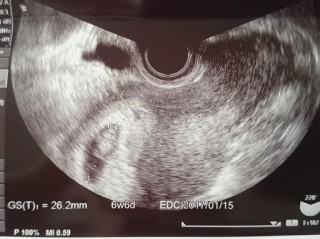

一週間前6w5dで胎嚢の中身が空っぽでした。 半分諦めて受診した7w5dで心拍、卵黄のう、胎芽の全てが確認出来ました! のちの数週訂正でこの時8w3dとなります。 胎嚢の大きさ的には6w6dとなっています。